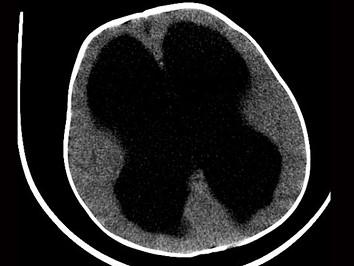

婴幼儿,女,头比一般孩子大,请结合影像图像选择最可能的诊断 ( )A、先天发育异常B、脑囊肿C、阻塞性脑积水D、交通性脑积水E、脑萎缩

问题 婴幼儿,女,头比一般孩子大,请结合影像图像选择最可能的诊断 ( )

选项 A、先天发育异常 B、脑囊肿 C、阻塞性脑积水 D、交通性脑积水 E、脑萎缩

答案 C